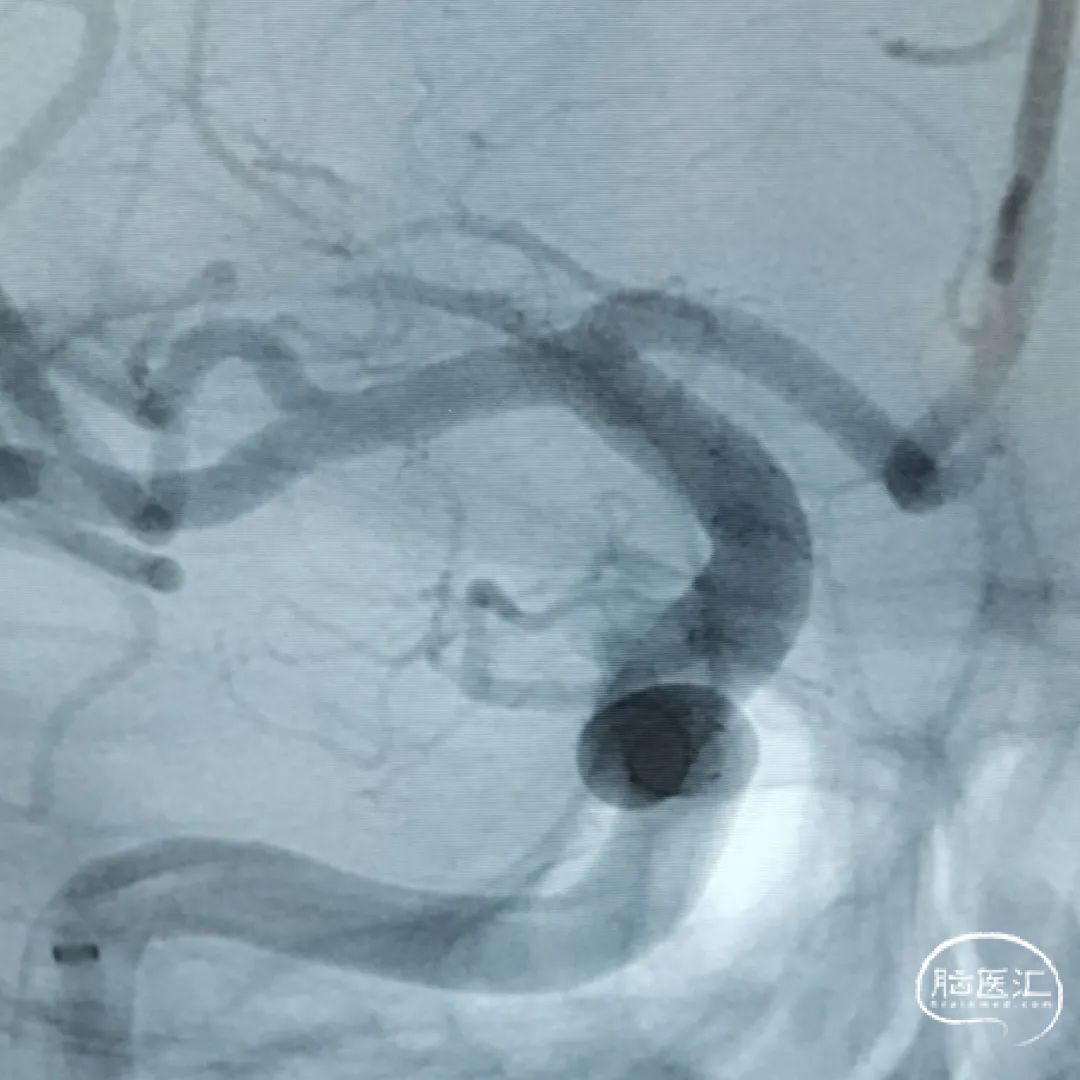

这是一根通桥银蛇DA远端通路导引导管,在Sim II和导丝到位后,通桥银蛇DA远端通路导引导管能够非常容易地顺着架设的道路直接放到位,然后进行后续使用Pipeline血流导向密网支架来治疗复发动脉瘤的操作。我们可以看到在Pipeline的到位以及释放的过程中,通桥银蛇DA远端通路导引导管都非常稳定,能够获得比较满意的结果。

释放PED过程中,通桥银蛇DA远端通路导引导管头端非常稳定。

术前

术后